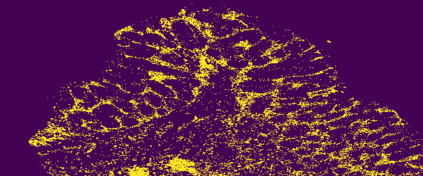

The usage of chemical imaging technologies is becoming a routine accompaniment to traditional methods in pathology. Significant technological advances have developed these next generation techniques to provide rich, spatially resolved, multidimensional chemical images. The rise of digital pathology has significantly enhanced the synergy of these imaging modalities with optical microscopy and immunohistochemistry, enhancing our understanding of the biological mechanisms and progression of diseases. Techniques such as imaging mass cytometry provide labelled multidimensional (multiplex) images of specific components used in conjunction with digital pathology techniques. These powerful techniques generate a wealth of high dimensional data that create significant challenges in data analysis. Unsupervised methods such as clustering are an attractive way to analyse these data, however, they require the selection of parameters such as the number of clusters. Here we propose a methodology to estimate the number of clusters in an automatic data-driven manner using a deep sparse autoencoder to embed the data into a lower dimensional space. We compute the density of regions in the embedded space, the majority of which are empty, enabling the high density regions to be detected as outliers and provide an estimate for the number of clusters. This framework provides a fully unsupervised and data-driven method to analyse multidimensional data. In this work we demonstrate our method using 45 multiplex imaging mass cytometry datasets. Moreover, our model is trained using only one of the datasets and the learned embedding is applied to the remaining 44 images providing an efficient process for data analysis. Finally, we demonstrate the high computational efficiency of our method which is two orders of magnitude faster than estimating via computing the sum squared distances as a function of cluster number.